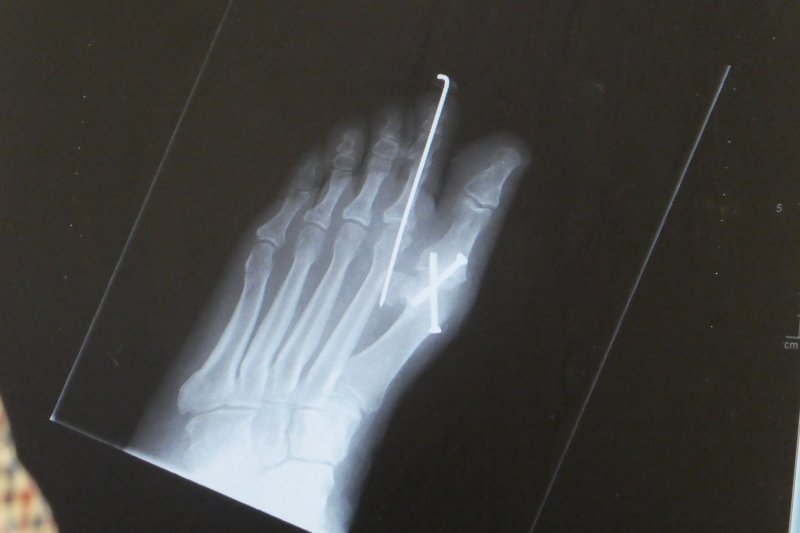

Yes the foot looks terrible with all the dry skin and the top part is a darker colour and I will never be able to bend the big toe with the two screws in it so will have to learn to walk differently:sad:

IMG_0647.JPG Hi @Upsydaisy glad that you have been signed off and all is well:blue thumb:

I haven't done any walking apart from round to our back garden and out the front.I desperately want to walk further but can't do it yet:sad: last evening I felt a jabbing pain in my toe as if my toe was being stabbed by a needle and was worried in case the screws were doing it under the skin:gaah: